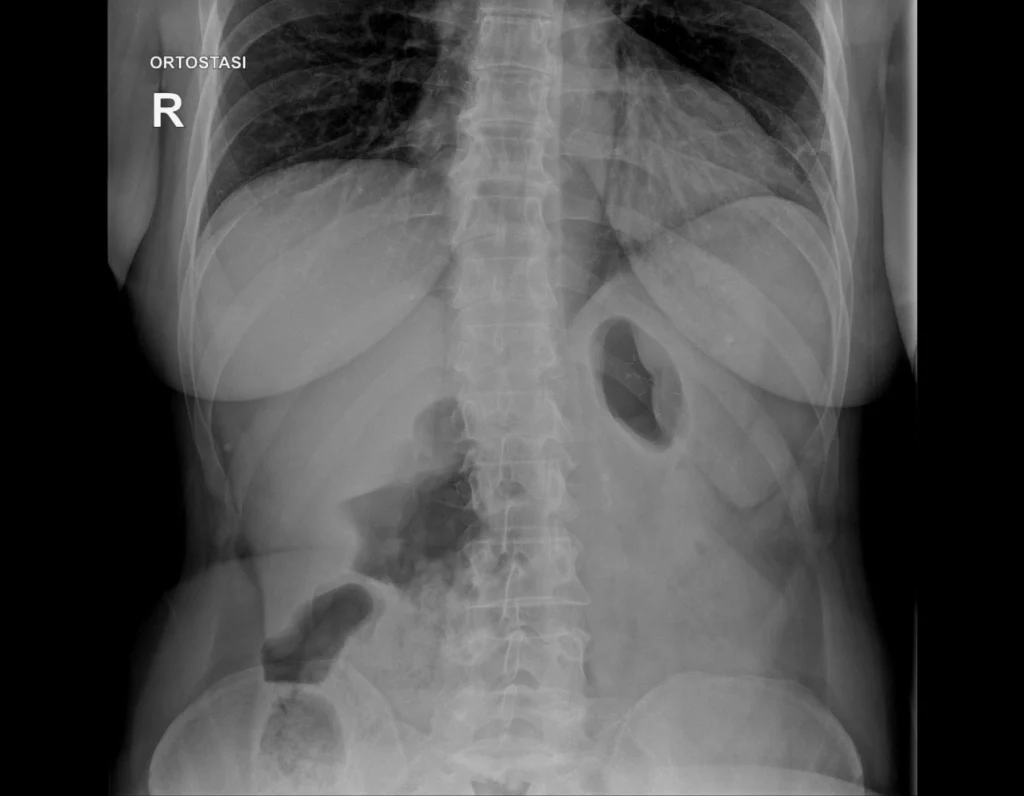

Radiografía simple de abdomen utilizada como ejemplo docente para identificar la densidad grasa y su rol como contraste natural.

Se identifican áreas de densidad intermedia, ligeramente más radiolúcidas que las partes blandas, correspondientes al tejido adiposo, que delimita y separa las estructuras abdominales.

La grasa presenta una atenuación mayor que el aire y menor que las partes blandas, por lo que se visualiza como un gris oscuro en la radiografía.

Su presencia permite delimitar órganos y planos anatómicos, actuando como un contraste natural.

- La grasa es más radiolúcida que las partes blandas.

- Se visualiza como un gris oscuro.

- Facilita la identificación de estructuras abdominales.